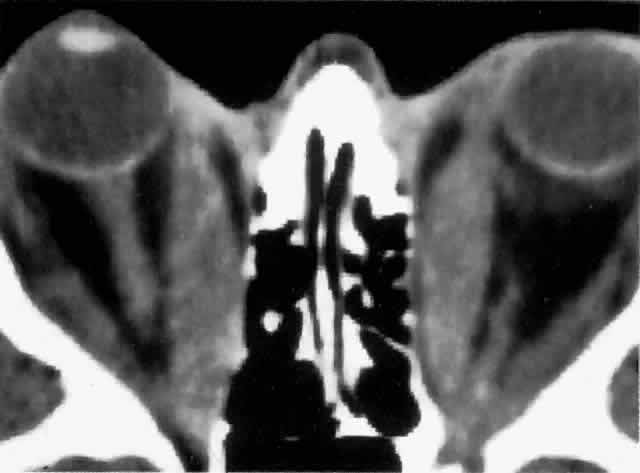

Computed tomography (CT), most revealing in the coronal plane, and ultrasonography are useful methods for assessing extraocular muscle thickness (Fig. 4). Magnetic resonance imaging (MRI) has been advocated as a means of differentiating between extraocular muscles that are actively inflamed and those that are fibrosed25–27; both muscular problems can restrict ocular movement, but the former is amenable to immunosuppressive intervention. The T2 relaxation time of MRI is directly proportional to the water content of the tissue scanned: since inflamed tissues are edematous, they should have longer T2 times. MRI is also thought to be better than CT in providing views of the orbital apex and may therefore be better for evaluating optic nerve compression.2

Fig. 4. CT scan through the orbits of a patient with thyroid-associated ophthalmopathy, showing bilateral exophthalmos with considerably thickened medial rectus muscles. (Courtesy of Mr. Peter Fells, Moorfields Eye Hospital, London.)